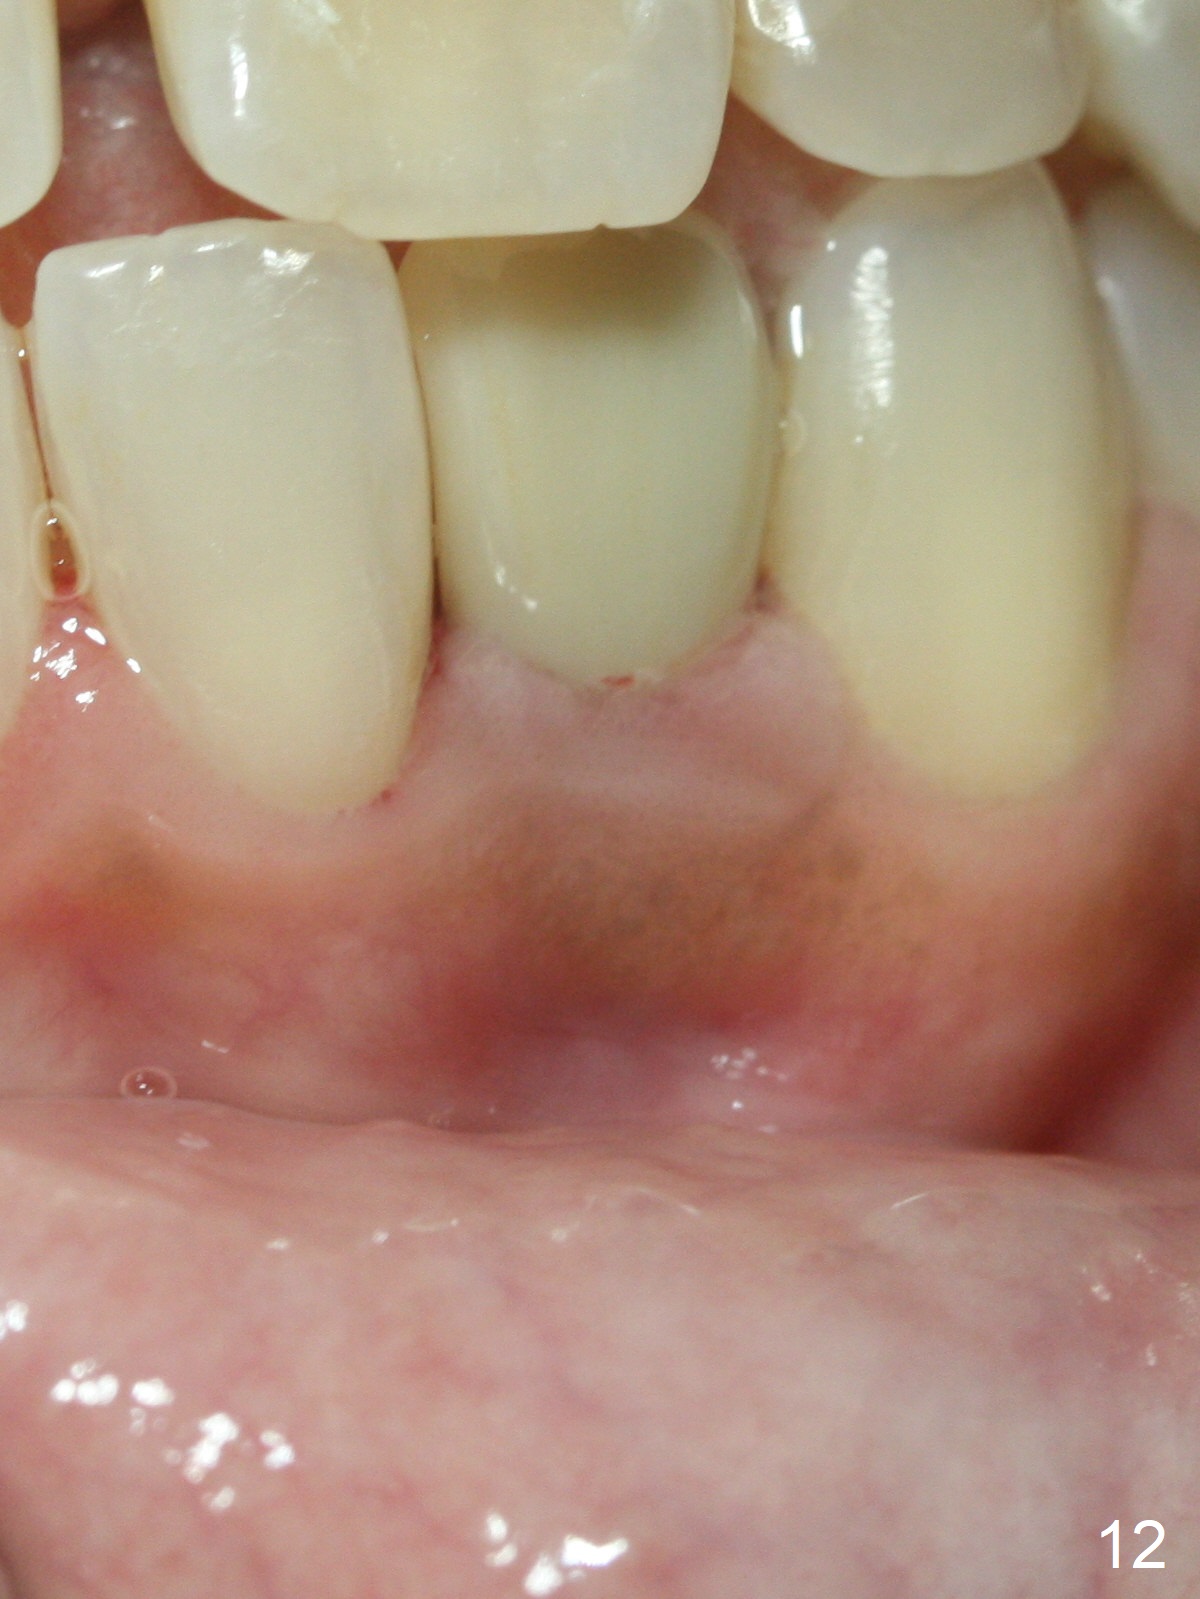

Fig.10: A2 shade guide. The patient requests A1 for the incisal edge and body and A2.5 for the cervical region. Fig.11 is taken 22 months post 2nd cementation (4 years postop). The implant crown remains normal 1 year 10 months post 2nd cementation (4 years 10 months postop, Fig.12,13).